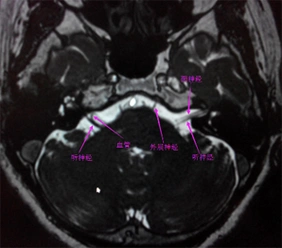

面神经解剖与常见疾病

面神经解剖及相关病变